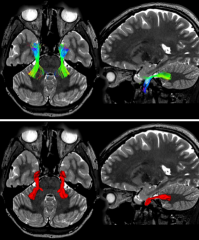

Refer to caption

Figure 4: Reconstruction results of the proposed CN atlas in a 28-year-old woman PA patient data. (a) Mapping results of 5 pairs of CNs pathways overlaid on the transverse plane of the T1w image. (b) Mapping results of the CN II pathway surrounding the tumor, and the tumor is red color. The upper right and lower right panels are magnified views of different perspectives of the relationship between the tumor and the nerve pathway in selected areas.

5.4 Performance on two PA Patients

In this experiment, we select two PA patients and use the proposed CN atlas to automatically identify the CN II surrounding the tumor. Regarding identification rate, Table 1 indicates that the proposed CN atlas successfully identified all CN II-D (2/2) and CN II-N (2/2) tracts of CN II subdivisions. For CN II visualization, Fig. 4 shows the different slices of the reconstruction results of the CN II pathway surrounding the tumor. From these results, we can find that the proposed CN atlas successfully identified different CN II subdivisions that surround the tumor.

We establish the anatomical validity of the proposed CN atlas in recognizing 5 pairs of CNs through multiple lines of evidence. First, the automatically identified CNs show high comparability to manual CN selection results, with visually similar fiber trajectories and strong spatial overlap (Fig. 3). Second, the anatomical validity of automatically recognized CNs was confirmed in patient data. As shown in Fig. 4, when a tumor compressed the optic nerve (CN II) along its pathway between the optic chiasm and lateral geniculate nucleus, our method successfully reconstructed the surrounding nerve fibers. This capability is critical for preoperative tumor resection planning. Finally, intraoperative validation in a CP patient confirmed that automatically identified nerves maintained clear spatial relationships with tumor locations.